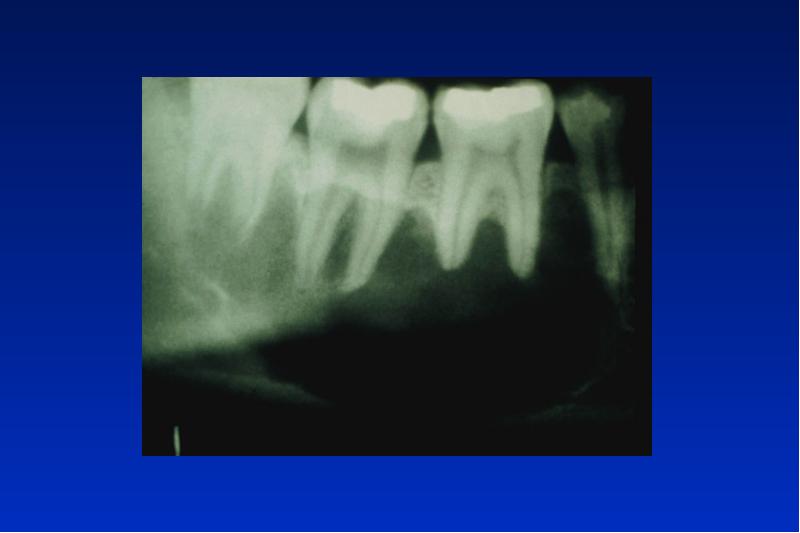

- 21. Odontogene Keratozyste Lok: UK Alter: 20 - 30, 50 - 60